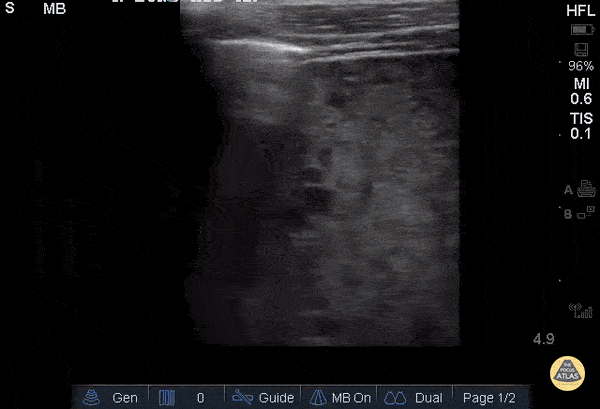

53yoM with 20+ year history of tobacco and alcohol abuse and newly diagnosed SCC presenting with productive cough and cachexia, found to have multifocal pneumonia likely due to aspiration. Mid-axillary ultrasound of the right lung using linear 13-6 MHz probe in the longitudinal plane demonstrating hepatization of the lung (right) and focal consolidation adjacent to normal lung parenchyma (left). US has high SEN (88%) and SPE (86%) for detecting pneumonia when compared to CXR or chest CT. (Ling 2017)